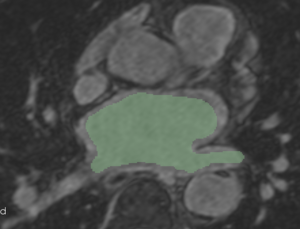

Example 2

Checker-filter: Pre and registered post LGE images Checker-filter: Pre and registered post LGE images Pre segmentation overlaid on registered post LGE

CARMA VecReg Check2.png

CARMA VecReg Check2-2.png

CARMA VecReg Seg2.png